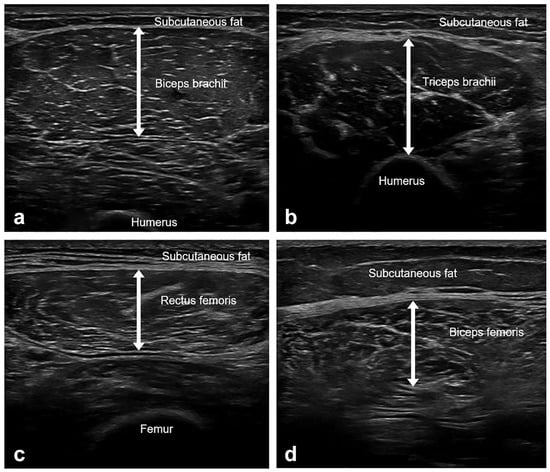

The thickness of four muscles (biceps brachii, triceps brachii, rectus femoris, and biceps femoris) was measured on the dominant side using B-mode US imaging (Aplio i700, Canon, Otawara, Japan) with an 18-Mz linear array transducer (Figure 1). The participants were examined with full relaxation, shoulder and hip in the neutral position, and elbows and knees in full extension. The biceps brachii (BB), triceps brachii (TB), and rectus femoris (RF) were examined in the supine position, while the biceps femoris (BF) was examined in the prone position. Care was taken to apply minimal pressure on the skin and to keep the probe as perpendicular to the skin as possible throughout the examination. The muscle thickness was assessed using the following anatomical landmarks (BB, between the medial acromion and the cubital fossa at 1/3 distance from the cubital fossa; lateral head of TB, at the midpoint between the posterior crista of the acromion and the olecranon at 2 finger widths lateral to the line; RF, at the midpoint between the anterior superior iliac spine and superior aspect of the patella; and the long head of BF, at the midpoint between the ischial tuberosity and the lateral epicondyle of the tibia). The muscle thickness was measured at the maximal muscle bulk with the probe positioned on the transverse plane of the muscles. Muscle thickness refers to the distance between the deep and superficial aponeuroses of a muscle.

Figure 1.

Representative images of muscle ultrasound and muscle thickness measurements. (a) Biceps brachii, between the medial acromion and the cubital fossa at 1/3 distance from the cubital fossa. (b) Triceps brachii, at the midpoint between the posterior crista of the acromion and the olecranon at 2 finger widths lateral to the line. (c) Rectus femoris, at the midpoint between the anterior superior iliac spine and the superior aspect of the patella. (d) Biceps femoris, at the midpoint between the ischial tuberosity and the lateral epicondyle of the tibia. Muscle thickness was defined as the distance between the deep and superficial aponeurosis of the muscle. The measurements were taken at their maximal muscle bulk.